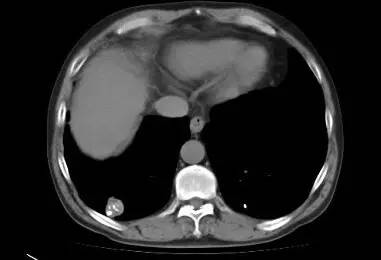

男,52岁,查体发现肺部病变

[影像描述]

右肺下叶结节样病变,内有钙化、脂肪成分,增强后可见轻度强化。

[检查结果]

右肺下叶错构瘤.

右肺下叶病变内有钙化、脂肪成分,典型爆米花样钙化,增强后可见轻度强化。